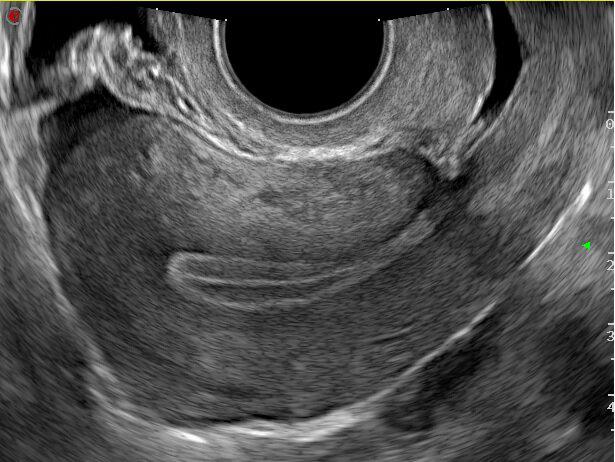

Los avances en este capítulo son extraordinarios. Bien empleados, puede decirse que muy pocas mujeres quedan sin diagnóstico en el caso de presentar patologías. La antigua "laparotomía exploradora" como método para establecer la causa de una enfermedad ginecológica, ha desaparecido en la actualidad. Ya no se concibe operar sin diagnóstico previo. Los avances continuos en el campo de las imágenes, nos permite conocer con creciente precisión, la condición de los órganos genitales pelvianos femeninos. La ecografía es el primer gran auxiliar, indispensable casi, para evaluar el estado anátomofuncional de útero y ovarios por vía abdominal transvesical en mujeres delgadas y sin relaciones sexuales o por vía transvaginal, en aquellas con actividad sexual que aceptan esta vía o en obesas, donde el espesor de la pared abdominal dificulta una buena visualización. En las figuras 1, 2, 3 4, 5 observamos ejemplos de genitales normales y de alguna patología. Hoy día la técnica denominada 4D brinda imágenes excelentes por lo que es empleada con frecuencia en el estudio morfológico del feto en su tercer trimestre.